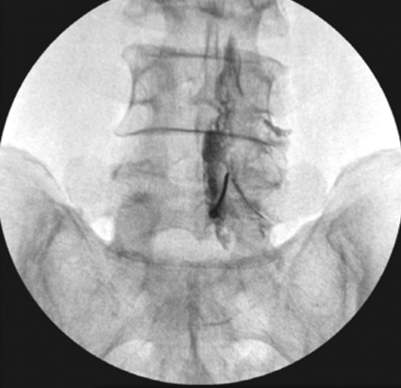

Effectiveness of Epidural Methylprednisolone Injection in Management of Lumbar Prolapsed Intervertebral Disc: A Comparison of Caudal, Transforaminal and Interlaminar Routes

Mrudul Kyada , Ketan Rupala , Akshay Bhatiya , Rahul Yadav , Naresh C Arora , Sansar Chand Sharma

………………………………p.441-449